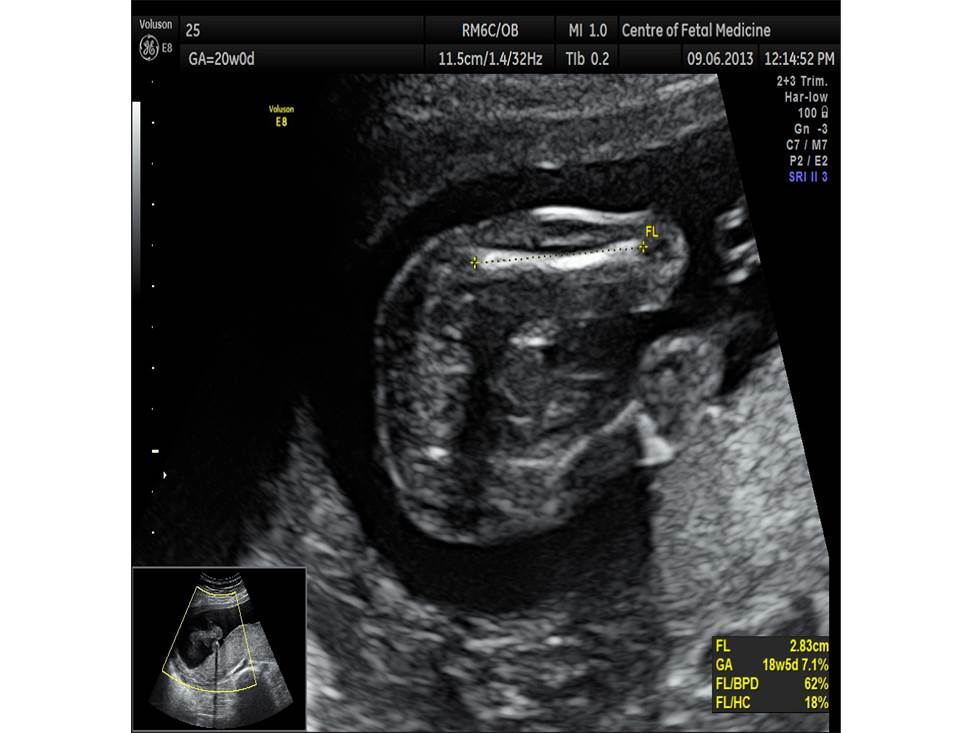

Вопрос 4

- Проанализируйте изображения плода в 20 недель, есть ли у него какие-либо маркеры хромосомной патологии?

- Необходимо ли рекомендовать инвазивную диагностику? Пациентке 25 лет, в 1 триместре не обследовалась